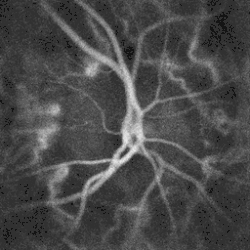

![]() Ophthalmoscopy photograph showing the optic disc as a bright area on the right where blood vessels converge. | |

The optic disc or optic nerve head is the point of exit for ganglion cell axons leaving the eye. Because there are no rods or cones overlying the optic disc, it corresponds to a small blind spot in each eye.

The ganglion cell axons form the optic nerve after they leave the eye. The optic disc represents the beginning of the optic nerve and is the point where the axons of retinal ganglion cells come together. The optic disc in a normal human eye carries 1–1.2 million afferent nerve fibers from the eye toward the brain. The optic disc is also the entry point for the major arteries that supply the retina with blood, and the exit point for the veins from the retina.[1]